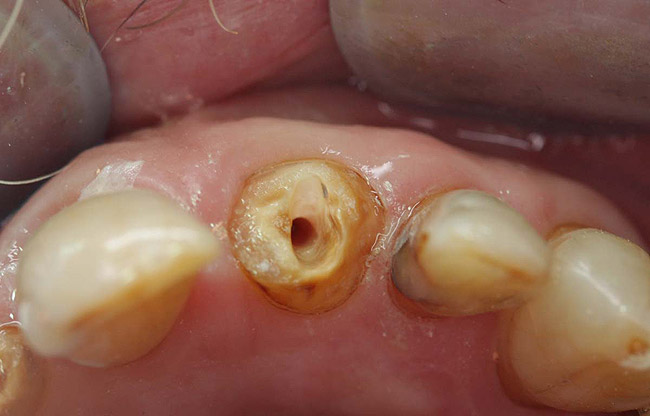

Case 4

A terminally ill patient presented an abscess on the maxillary right central incisor. Endodontic treatment was completed with a composite restoration placed to restore the access hole. The crown fractured off within 1 week (Figure 15 and Figure 16). Gutta-percha was removed, and the canal prepared to accept a C-1 white post (Figure 17). The root was bonded with BRUSH and BOND™ (Parkell, www.parkell.com) and the post was cemented with a resin cement (Figure 18). Absolute Dentin core build-up material was applied (Figure 19). There are many different build-up materials, including glass ionomers such as Ketac-Silver™ (3M ESPE, www.3mespe.com) or Miracle Mix® (GC America, www.gcamerica.com), pastes that are mixed such as Zenith (Carson Dental, www.carsondental.com), and automix syringes such as Absolute Dentin. The material was of a consistency that allows placement without sagging or running (Figure 20). It was light-cured and prepared for temporization (Figure 21) and the final all-composite restoration was delivered (Figure 22).

Figure 15  Fractured tooth in a crown of a recently treated endodontically central incisor.

Figure 15

Figure 16  The fractured central incisor root.

Figure 16